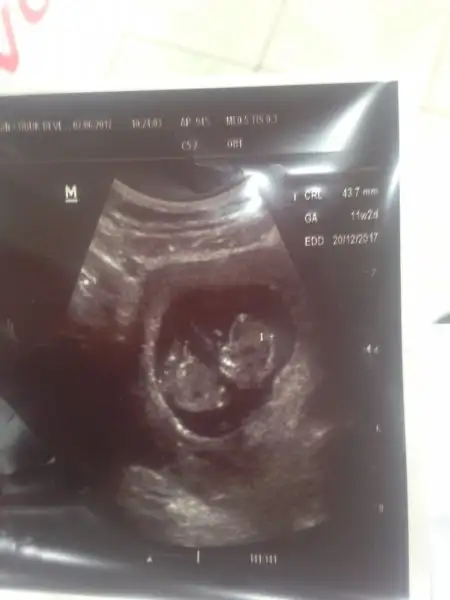

Insallah cnm ınsallah sılemstrde ben duymamamdr kagt dpldrdu sekreter hc bakmadım heyecandan kan vergm yere verdm onuda. Bebekle ılgıılıde consoyete erken dedı gornmuyo dımı Fotoda

Merhaba sonunda aradihim basligi buldum bende aralikta dogum yapicam insaallah. 11+4 benimkide daha ikili test yaptirmadim. Cok rahatsizim mideden dolayi buna birde bir haftafir bogazin ic taraflaridaki agri ve dislerime vuran agri ile kabisa dondu nasil basadecegimi bilemez oldum.